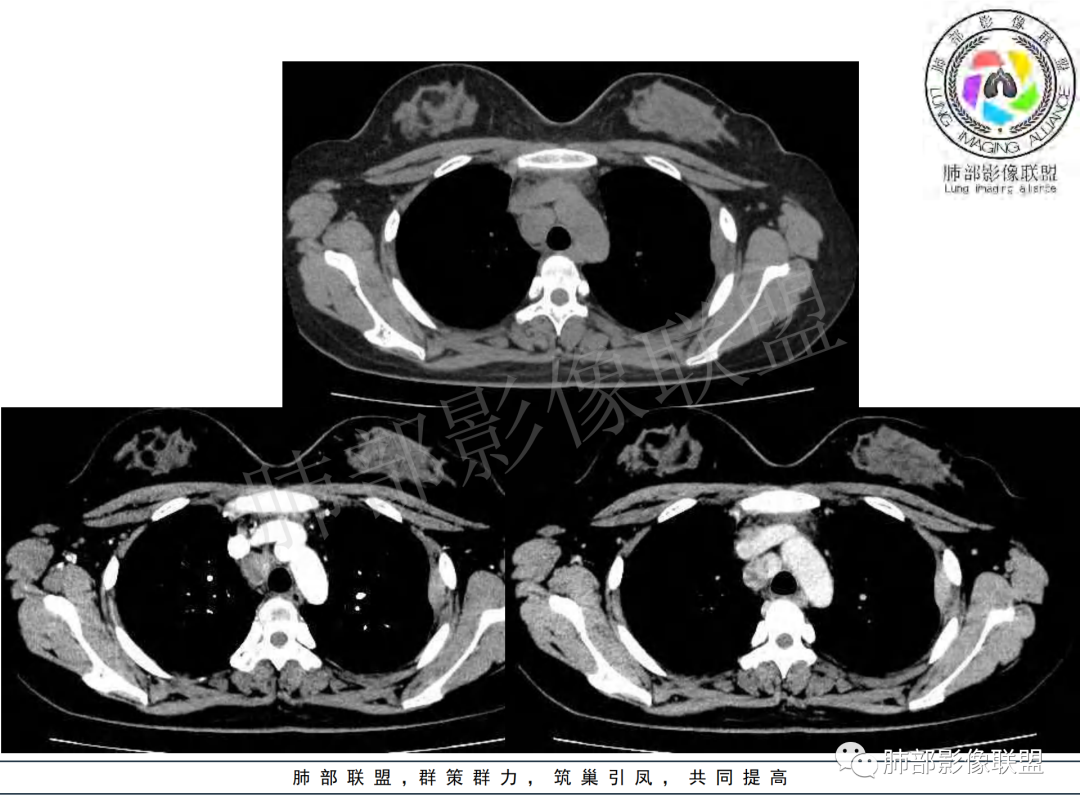

纵隔多组及右侧肺门多发肿大淋巴结,部分融合,不均匀强化,内见斑片状坏死区及环状强化,后者坏死边界尚清晰,肺门区肿大淋巴结与肺组织边界不清,年轻女性,8个月病史,发热首发症状,考虑淋巴结核并向肺内侵及(破溃?),鉴别淋巴瘤

女,20,病程长达8月,发热、胸痛、右侧胸腔积液病史。胸部CT:右肺门旁不规则肿块影,右中间支气管腔内结节,纵隔多发淋巴结肿大;强化不均匀,灶性坏死灶,环形强化;右侧少量胸腔积液并局部肉芽肿样突起。年轻女性,长病程,多部位,考虑慢性炎症,结核?鉴别肿瘤。

年轻女性,慢性病程,发热、胸痛。右肺门旁不规则肿块影,纵隔多发淋巴结肿大;强化不均匀,环形强化;右侧少量胸腔积液;首先考虑结核,鉴别肿瘤,结节病。

慢性病程,前纵隔右肺门旁多发淋巴结肿大;强化不均匀,环形强化;右侧少量胸腔积液;考虑结核,鉴别结节病。

青年女性,发热、胸痛、右侧胸腔积液病史,病程8个月。曾多次抗炎后均有好转。CT:右肺门旁肿块影,双侧胸膜结节,纵隔多发淋巴结肿大,边缘模糊;增强渐进性明显强化,纵膈淋巴结较彻底坏死灶,边缘环形强化。考虑结核,鉴别恶性肿瘤。

本例患者,年轻女性,慢性病程,多次抗感染治疗效果不佳,实验室检查示白细胞及中性粒细胞不高,不支持普通细菌感染,虽然肺泡灌洗液X-Pert检测阴性,结合患者胸部CT结核感染亦不能排除,胸部CT主要表现为右侧肺门及纵隔淋巴结肿大,仔细观察不难发现右中间支气管内新生物凸向管腔内,增强扫描,右肺门(10R)及纵隔淋巴结(2R,4R)明显不均匀强化,内部呈不规则低密度无强化区,被周边高强化区包绕(环形强化)的特点,首先应当想到纵隔淋巴结结核诊断。淋巴结分布亦不符合肺部恶性肿瘤迁徙途径。